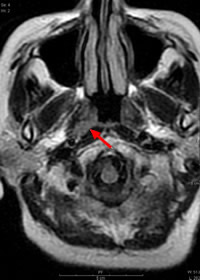

Ct検査よりがん組織と正常組織の区別が明確でct検査とは異なる情報からがんの深さや広がりリンパ節への転移の有無を調べます 7超音波エコー検査 首の表面から超音波をあ てそのはね返りをモニターで見ながら確認. 下咽頭癌の進展範囲を読影する際のチェックポイント 腫瘍の最大径 喉頭への進展の有無 軟骨浸潤の有無 上下方向への進展範囲の決定中咽頭頸部食道 軟部組織浸潤の有無特に梨状癌 梨状窩尖部への進展の有無.

頸部 Dual Energy Ctを用いた喉頭癌と下咽頭癌による喉頭軟骨浸潤評価